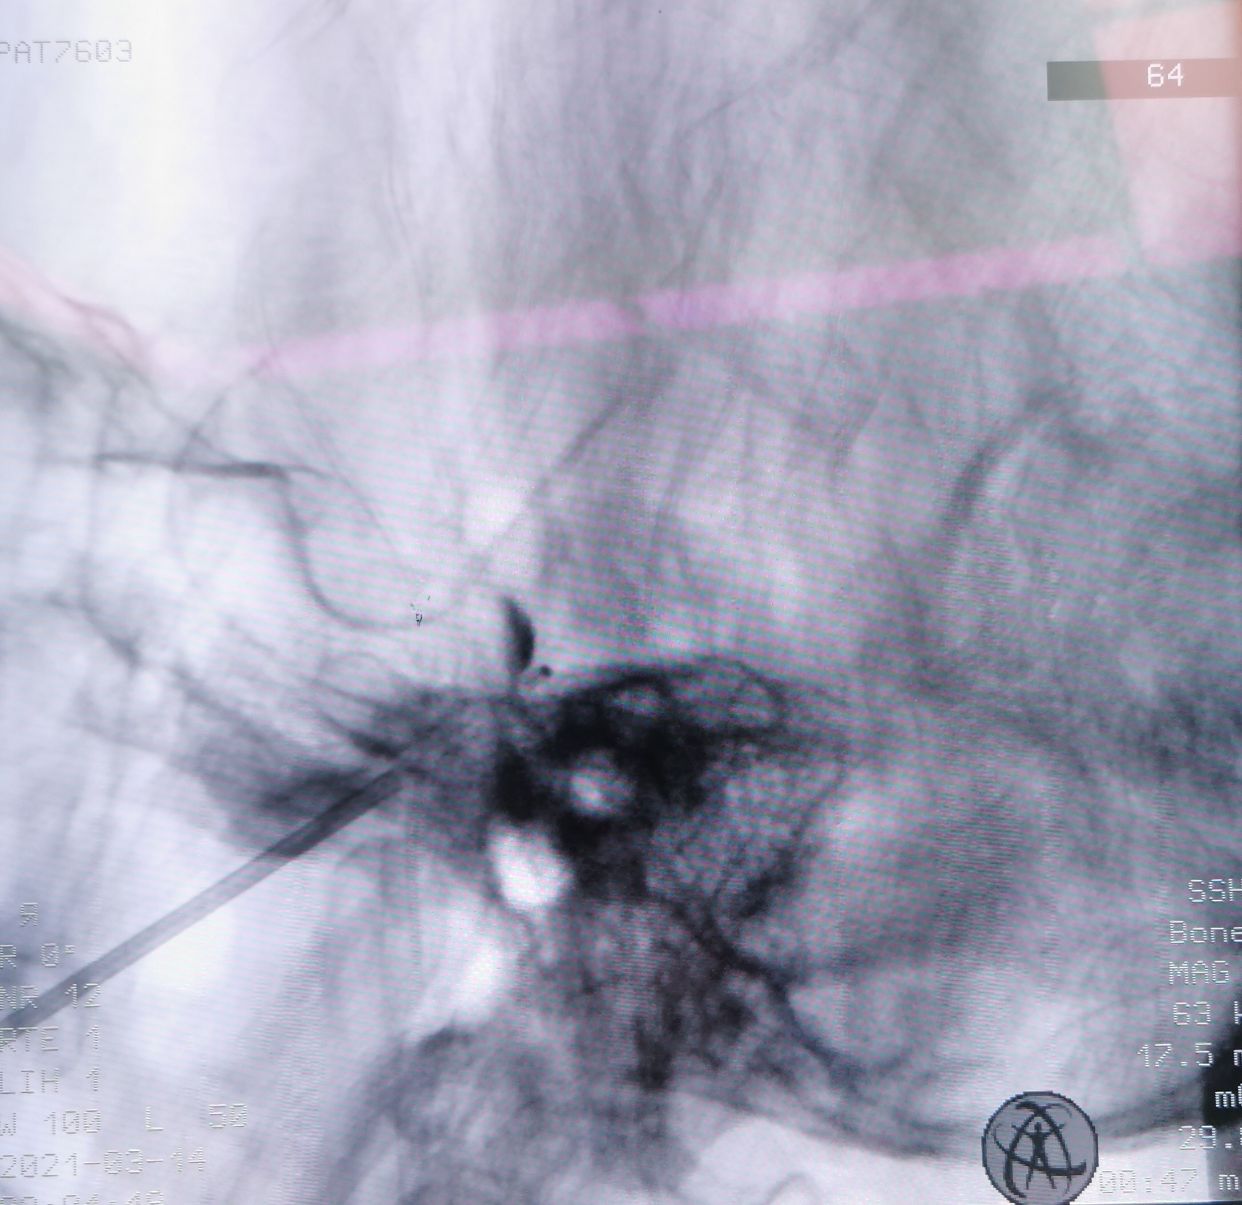

穿刺针到此,无法进入,骨质完全遮挡

改为中入路

成功